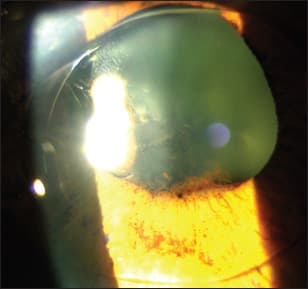

An older gentleman showed nothing striking on the slit lamp exam, but a dilated exam showed an iris pigmented epithelium bulging that turned out to be an iris cyst on the UBM. However, an anterior segment OCT image did not give us the diagnosis. The resolution of the cornea and the visualization of the angle were very good, but the OCT didn't allow complete visualization. The posterior wall of the cyst was not visible. So we couldn't tell exactly how big it was or what was behind it. The UBM's depth of penetration offers complete visualization of different iris pathologic conditions, as well as the IOL and haptics placement (Figure 1).

Figure 1. This 88-year-old patient has a large iris cyst. The dilated exam shows a bulging of the iris. The anterior segment OCT image does not give us the diagnosis. However, the UBM's depth of penetration allows imaging of this large iris cyst, as well as the intraocular lens and haptic placement.